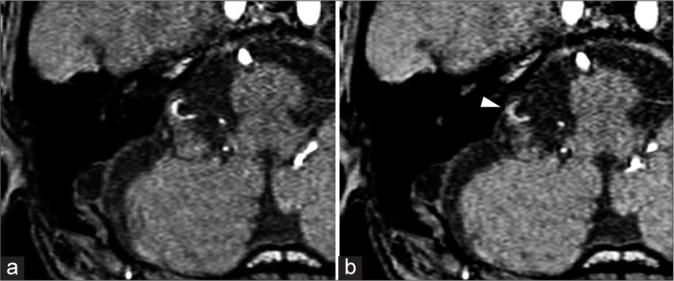

A 68-year-old man who underwent SRS for VS 20 years ago presented with subarachnoid hemorrhage (SAH) due to rupture of a radiation-induced fusiform anterior inferior cerebellar artery aneurysm. He was treated with parent artery occlusion, resulting in a modified Rankin scale grade 2. This report illustrates the first case of detected aneurysm formation before rupture with retrospective magnetic resonance imaging evaluation.

一名20年前接受SRS治疗VS的68岁男性,因放射性诱发的梭形小脑前下动脉瘤破裂出现蛛网膜下腔出血(SAH)。他接受了供血动脉闭塞治疗,结果改良Rankin量表评分为2级。本报告阐述了首例通过回顾性磁共振成像评估在破裂前检测到动脉瘤形成的病例。